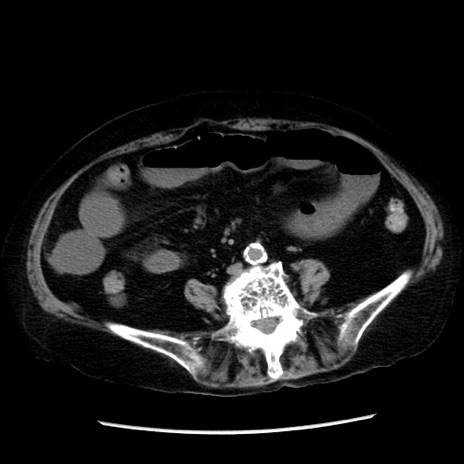

症例14(横断像)

【症例】 90歳代女性

【主訴】 腹痛・嘔吐

【現病歴】今朝から左側腹部痛を認めた。 経過観察していたが、嘔吐を認めたため来院。

【既往歴】 子宮癌術後

【身体所見】 意識清明、BP 127/54mmHg、P 98bpm Sp02 95%(RA)、BT 35.8°C、腹部平坦・軟腸ぜん動音聴取良好、右下腹部圧痛(+) 反跳痛なし

【データ】WBC 9800、CRP 0.46